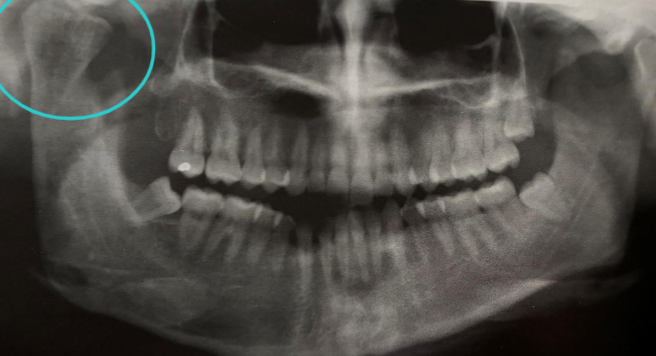

condylar hyperplasia

excessive growth of condyle due to NEOPLASM/ ENDOCRINE distubances